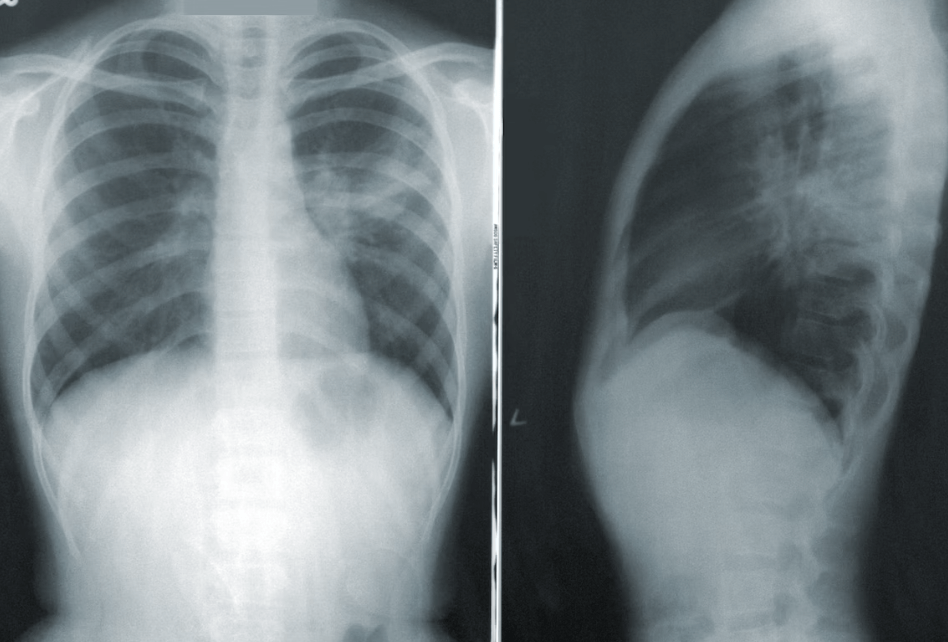

폐 결절은 흉부 X-레이 또는 CT 스캔과 같은 폐 영상에서 점 또는 "동전 병변"으로 나타나는 작고 둥글거나 타원형의 성장물입니다. 이 결절의 크기는 몇 밀리미터에서 3센티미터까지 다양합니다. 매우 흔하며 대부분 양성입니다(비암성). 그러나 일부 결절은 악성(암성)이거나 시간이 지남에 따라 암이 될 가능성이 있습니다.